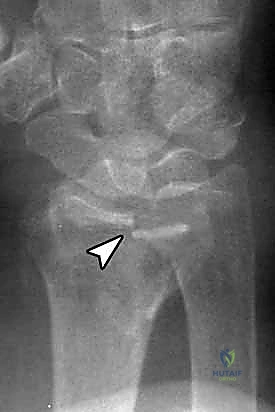

تُعرف كسور الكعبرة البعيدة بأنها تشمل منطقة الكردوس (Metaphysis)، وتحديداً المنطقة الواقعة ضمن طول السطح المفصلي الذي يعادل أوسع جزء من الرسغ بأكمله. في عياداتنا، نقوم بتقييم هذه الكسور بدقة متناهية بناءً على عدة خصائص رئيسية تحدد مسار العلاج:

يعتمد الدكتور محمد هطيف على أحدث التقنيات التشخيصية، حيث يبدأ بـ الأشعة السينية (X-rays) في وضعيات متعددة. وفي حالات الكسور المعقدة التي تمتد إلى داخل المفصل، يتم إجراء تصوير مقطعي محوسب (CT Scan) لبناء صورة ثلاثية الأبعاد للكسر، مما يساعد في التخطيط الجراحي الدقيق.